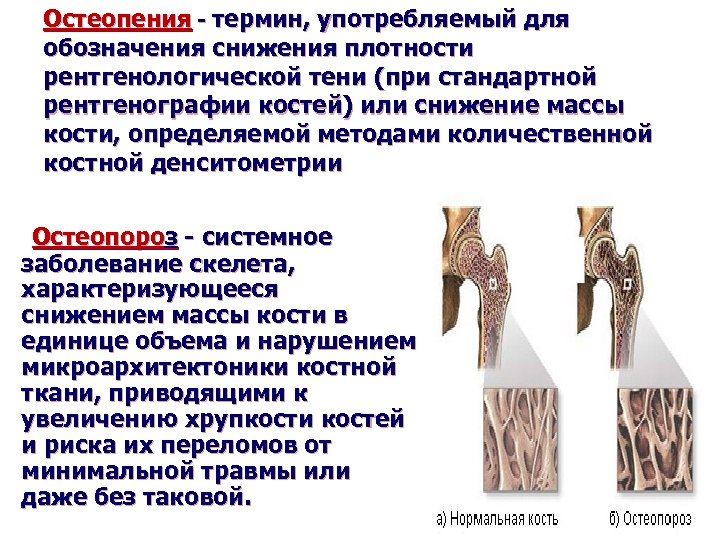

Иллюстрации и снимки, связанные с остеопенией шейки бедра